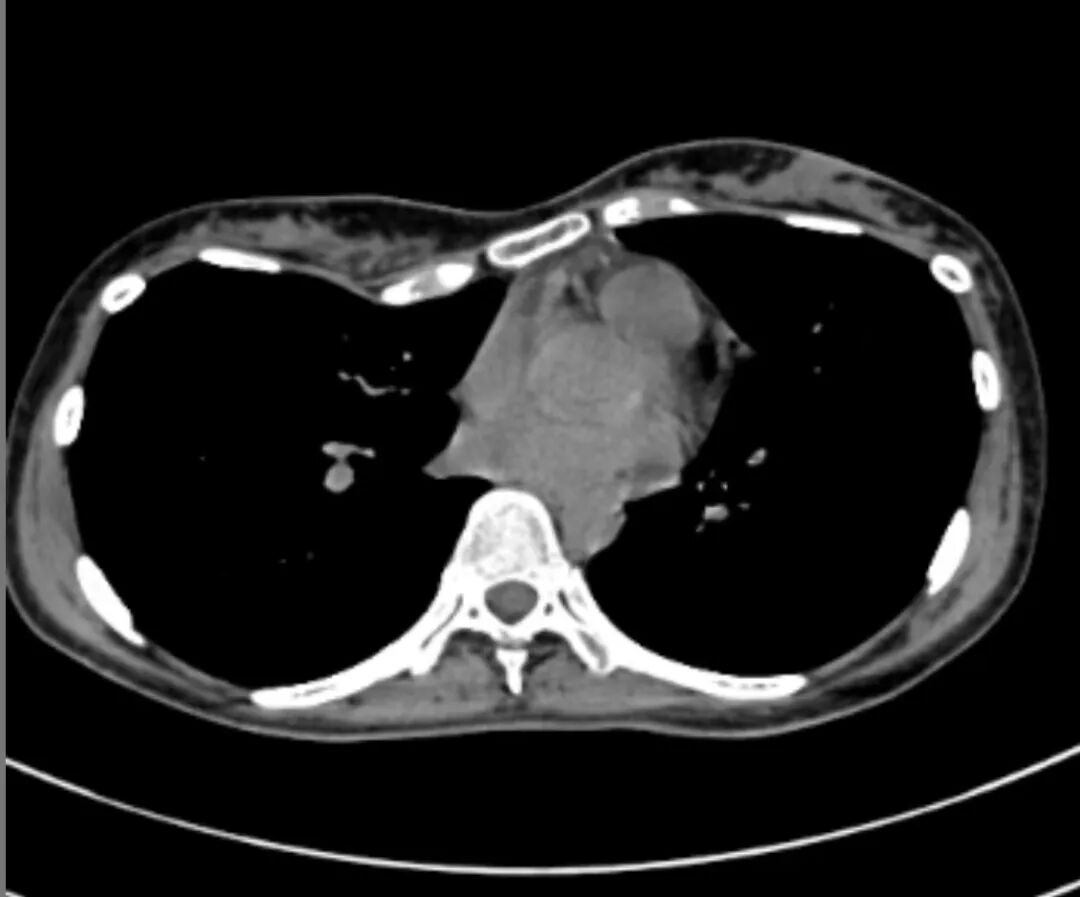

术前检查显示,李女士前胸壁呈显著不对称凹陷,最深点位于右侧,心脏受压移位明显。团队综合评估后,决定采用国际领先的Wung手术方案。手术在全麻下实施,王文林教授亲自主刀,于侧胸壁做切口。经侧胸壁精准入路,全程保护乳腺及软组织,巧妙植入两块特制钢板,同步矫正凹陷与不对称。全程仅40分钟,零输血、零并发症,术后畸形彻底消失。